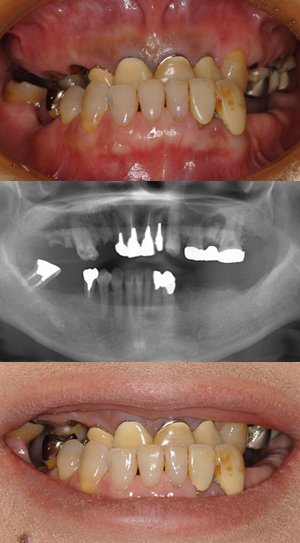

オールオン4症例①

1. all on 4治療前

2. all on 4治療後

主訴 歯周病にて歯がなくなってしまい物が噛めない

治療内容 残っていた歯を全身麻酔下にてすべて抜歯して同時に上下8本のインプラントを埋入。 翌日に固定式の仮歯を装着した。 骨とインプラントが結合するのをまち、最終的な上部構造を装着した。

治療期間 9か月

治療金額

• 全身麻酔および1泊入院費用:

¥220,000(税込)

• ALL on 4 手術費用:

¥1,210,000(税込)

• 上部構造(チタンe-maxタイプ)

¥1,870,000(税込)